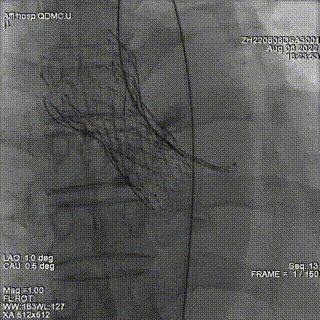

结合术前CTA评估,在S曲线中确定左冠切线位投照角度为LAO32 CRA6, 并在此角度下通过DSA引导导丝通过PVL。